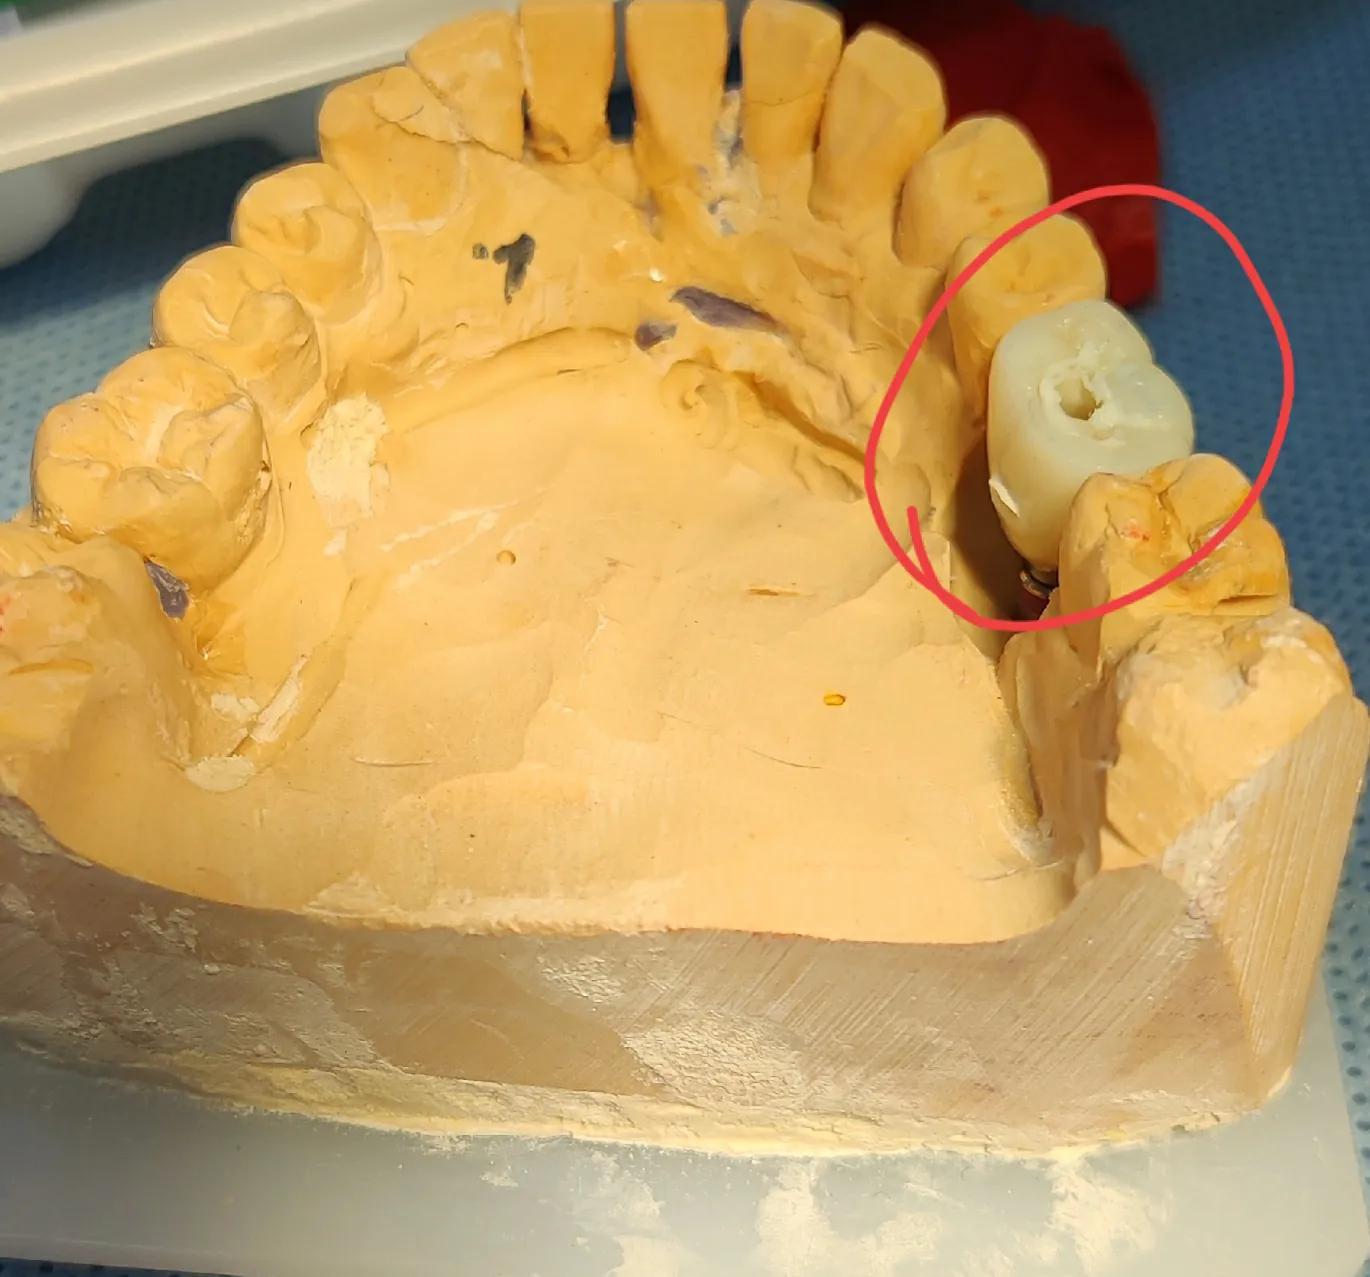

做好的牙齒模型

戴上牙冠